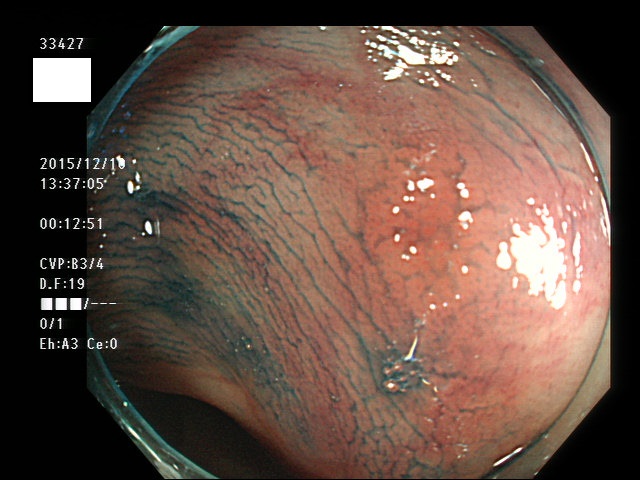

上記100名より抽出した平坦・陥凹型腺腫(=癌化の危険が高いが見落としやすい病変)の内視鏡写真